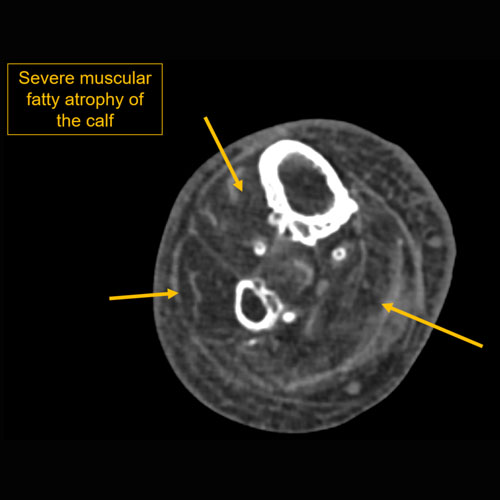

| Muscles | Correct Answer | Your Answer |

|---|---|---|

|

There is fatty atrophy. |

No | NA |